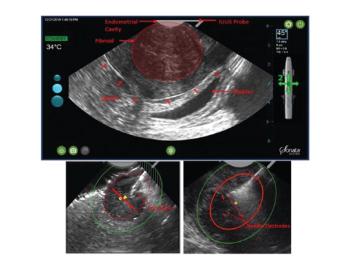

Understanding the technology behind a newer uterus-sparing option for the management of uterine fibroids.